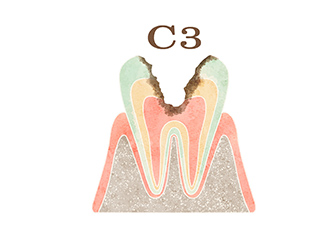

歯の内部に入った細菌を除去し、痛みや腫れを取り除く治療を行います。取り除いた部分には、歯型を取って作製した修復物を被せます。被せ物を安定させるために、歯の土台(コア)が必要になることがあります。

根管治療とは、歯の内部に入った細菌を除去し、痛みや腫れを取り除く治療です。主にC3~C4の段階のむし歯に対して行います。

むし歯菌に感染して、歯根の先に膿が溜まっている状態です。マイクロスコープを用いて、丁寧にむし歯を取り除きます。

ファイルと呼ばれる器具でむし歯菌によって感染した神経や血管を取り除き、根管長測定器で根の長さを測ります。

汚染された歯根を掃除し、細菌が残らないように専用の消毒液を使い、洗浄します。

消毒が終わったら、細菌が繁殖しないように充墳剤を入れて密封します。

被せ物が安定するように歯を削った部分を埋め、歯の欠損が大きい場合には歯の土台(コア)を造成します。

土台と適合する被せ物を作製します。被せ物を装着し、かみ合わせの確認をして治療終了です。